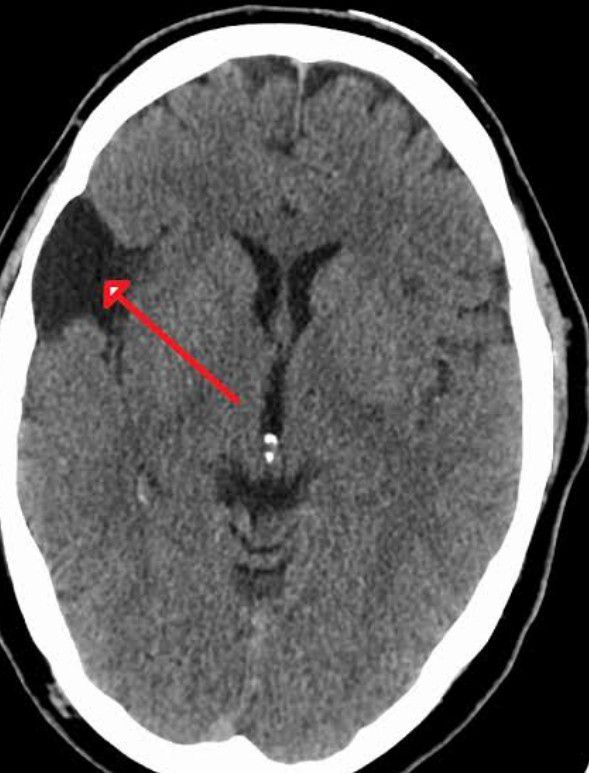

Symptoms of Arachnoid cysts

Typical symptoms of an arachnoid cyst around the brain include: Headache. Nausea and vomiting. Seizures. Hearing and visual disturbances. Vertigo. Difficulties with balance and walking.